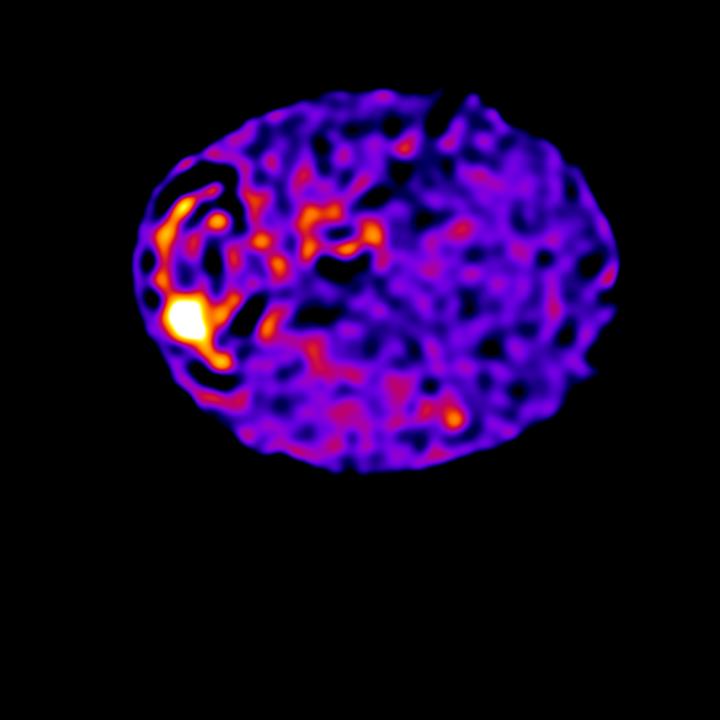

image: The first ever images of the cell-wide web have been captured by scientists at the University of Edinburgh thanks to computing techniques similar to those used for the first picture of a black hole. The findings reveal cells in the body are wired like computer chips to direct signals that instruct how they function. Unlike a fixed circuit board, however, cells can rapidly rewire their communication networks to change their behavior.

Researchers at the University of Edinburgh found information is carried across a web of guide wires that transmit signals across tiny, nanoscale distances.

It is the movement of charged molecules across these tiny distances that transmit information, just as in a computer microprocessor, the researchers say.

The team made their discovery by studying the movement of charged calcium molecules inside cells, which are the key messages that carry instructions inside cells.

Using high-powered microscopes, they were able to observe the wiring network with the help of computing techniques similar to those that enabled the first ever image of a black hole to be obtained.